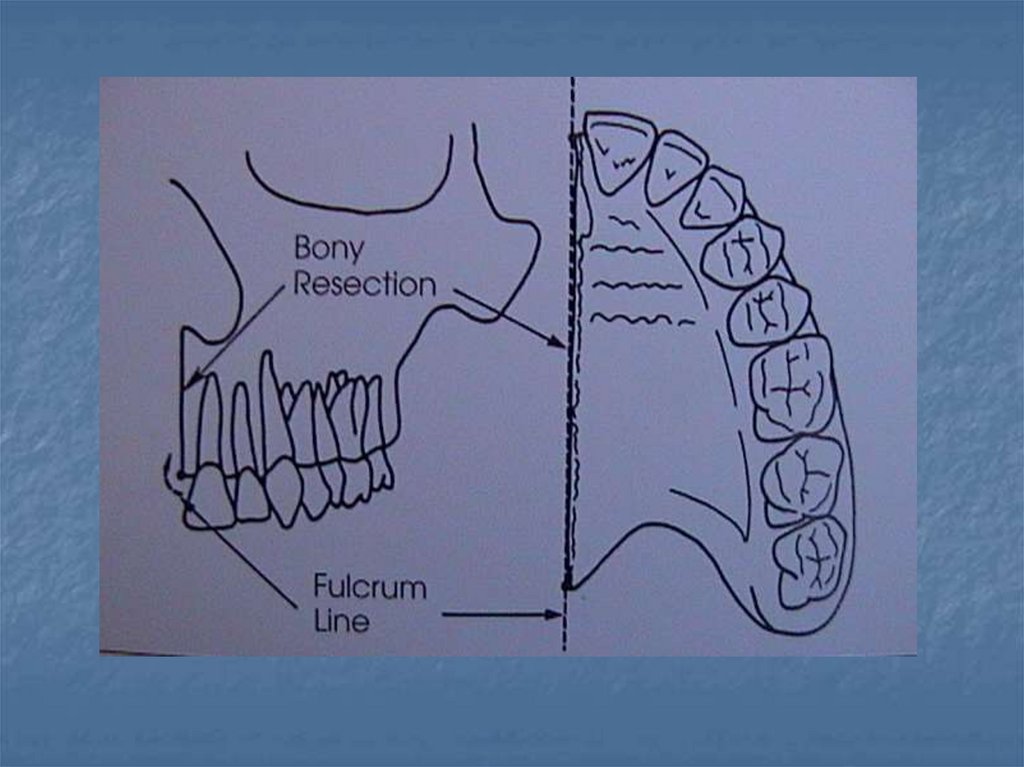

36. 5- Yan duvar yüksekliği

Defektin yan duvarı endirekt retansiyon için

kullanılabilir. Defektin yan duvarı obturatörün

arksal yer değiştirmesi ile oluşan basınca karşı

direnç oluşturur. Protezin defekt içindeki

retansiyonu "fulkrum" noktasını merkez kabul

eden ve bir yarı çap boyunca sürüklenen bir

noktanın dikey yer değiştirmesi ile meydana

gelir. Obturatörün yan duvar yüksekliği artırılırsa

protezin yer değiştirmesi (rotasyonu ) azaltılır.

39. Stabilite

Protezin yatay düzlem

etrafındaki rotasyonu

fullkrum çizgisi

etrafında görülen

rotasyondur.

obtüratör planlaması,

retansiyon ve

stabiliteyi birlikte

sağlamaya yönelik

yapılmalıdır.